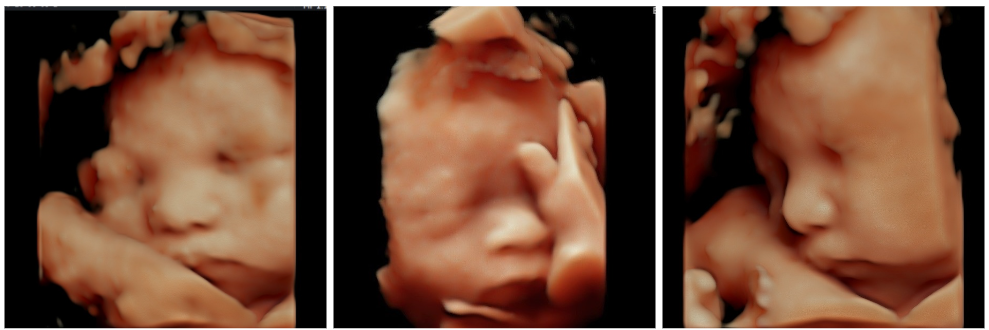

นอกจากนี้ใบหน้าของลูกจะชัดขึ้นมากๆ แล้วค่ะ คุณแม่ท่านไหนอยากเก็บภาพเป็นที่ระลึก แอดมินแนะนำให้ทำ “อัลตราซาวด์ 4 มิติ” ในช่วงนี้เลยนะคะ 😀

อัลตราซาวด์ 4 มิติ

– ใช้ในการดูรูปใบหน้า และลักษณะภายนอกของทารกได้ดี

– อาศัยการประมวลผลจากหัวตรวจชนิดพิเศษ

– ภาพมีลักษณะเป็น 3 มิติเสมือนจริง เป็นภาพนิ่ง สีเนื้อ

– มิติที่ 4 จะเป็นการถ่าย VDO แบบ Real-time ขณะตรวจค่ะ